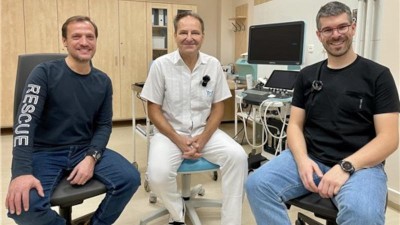

Marek stále neměl vyhráno, po amputaci jej čekala další operace ruky a druhé nohy. „Domů jej pustili 17. září, tedy měsíc po nehodě. Teď se učí být samostatný, rehabilituje. To vše stojí mnoho peněz, byli bychom šťastní, kdyby mohl získat kvalitní protézu, aby se mohl zase postavit na obě nohy," uzavírá Martina Vítková.